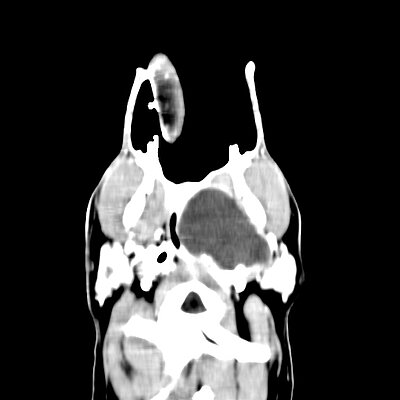

Bei der Untersuchung in Narkose fiel auf, dass der Bereich hinter dem Kehlkopf durch eine Masse, die von „außen“ an die Schleimhaut drückte, massiv eingeengt wurde, so dass die Atemwege zum Großteil verlegt waren. Im computertomographischen Bild zeigte sich, dass das komplette Mittelohr eitergefüllt und der Knochen bereits teilweise aufgelöst war. Ans Mittelohr anschließend hatte sich eine riesige Abszesshöhle gebildet, die zur Einengung der Atemwege führte. Als Ursache konnte eine Anomalie des äußeren Gehörkanals diagnostiziert werden: dieser ist bei „Barley“ nicht mit dem Mittelohr verbunden, sondern endet blind davor.